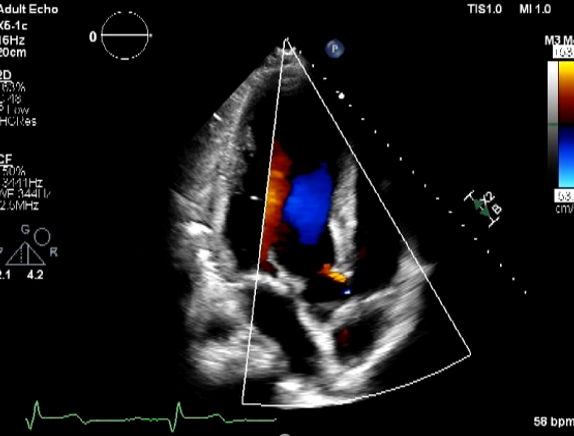

Relevant Test Results Prior to Catheterization

EKG showed normal sinus rhythm with ST segment elevation at V1-3 , inverted T wave at V4-6 , I ,aVL. Echocardiogram showed impaired LV systolic function, global wall hypokinesia, normal prosthetic aortic valve function with mild paravalvular leakage and bulging of aortomitral intervalvular fibrosa, suspected Aortomitral intervalvular fibrosa aneurysm. CT cardiac revealed pseudoaneurysm of the aortomitral intervalvular fibrosa with laminated thrombus with no LAA thrombus visualized.